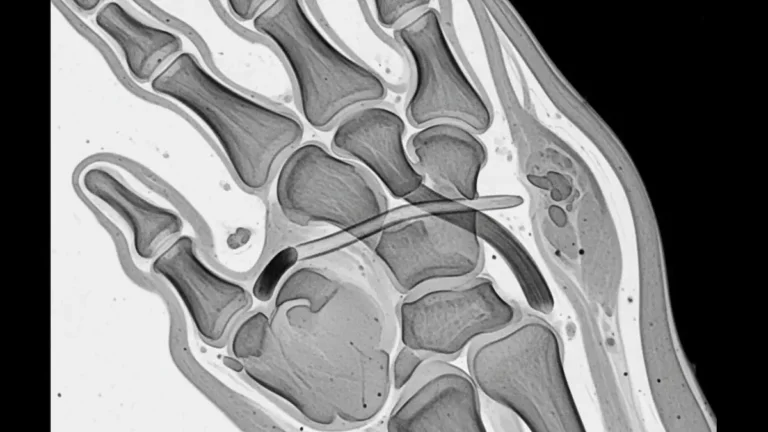

Fratura de boxer é o nome dado à quebra do colo do 5º metacarpo, o osso que liga o dedo mínimo ao punho. Ela costuma acontecer depois de um soco em superfície rígida, mas também pode surgir após quedas, pancadas…